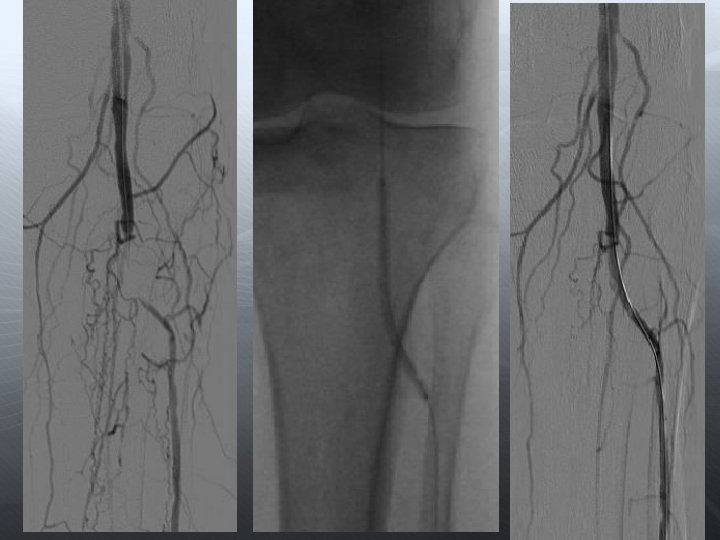

Darlık Oklüzyon Aorto-iliak Femoral-popliteal Infrapopliteal

Re-entry cihazı